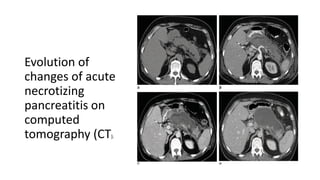

Evolution of

changes of acute

necrotizing

pancreatitis on

computed

tomography (CT).

1. CT scan of the abdomen without IV contrast performed on admission for

a patient with acute gallstone pancreatitis, showing mild peripancreatic

stranding.

2. Contrast-enhanced CT scan of the abdomen performed on the same

patient 1 week after admission shows extensive intrapancreatic necrosis,

evidenced by the lack of contrast enhancement in the pancreatic body

with very minimal enhancement noted at the distal most aspect of the

pancreatic tail.

3. Contrast-enhanced CT scan of the abdomen performed on the same

patient 2 weeks after admission demonstrates a semiorganized,

heterogeneous fluid collection, referred to as an acute necrotic

collection. On this image, a small area of viable pancreatic parenchyma is

seen at the tail of the pancreas.

4. Contrast-enhanced CT scan of the abdomen performed on the same

patient 5 weeks after admission demonstrates a well-encapsulated fluid

collection, essentially replacing the pancreas, referred to as walled-off

necrosis.

Evolution of changes ofacute necrotizing pancreatitis on computed tomography (CT).

1. CT scanof the abdomen without IV contrast performed on admission for a patient with acute gallstone pancreatitis, showing mild peripancreatic stranding. 2. Contrast-enhanced CT scan of the abdomen performed on the same patient 1 week after admission shows extensive intrapancreatic necrosis, evidenced by the lack of contrast enhancement in the pancreatic body with very minimal enhancement noted at the distal most aspect of the pancreatic tail. 3. Contrast-enhanced CT scan of the abdomen performed on the same patient 2 weeks after admission demonstrates a semiorganized, heterogeneous fluid collection, referred to as an acute necrotic collection. On this image, a small area of viable pancreatic parenchyma is seen at the tail of the pancreas. 4. Contrast-enhanced CT scan of the abdomen performed on the same patient 5 weeks after admission demonstrates a well-encapsulated fluid collection, essentially replacing the pancreas, referred to as walled-off necrosis.